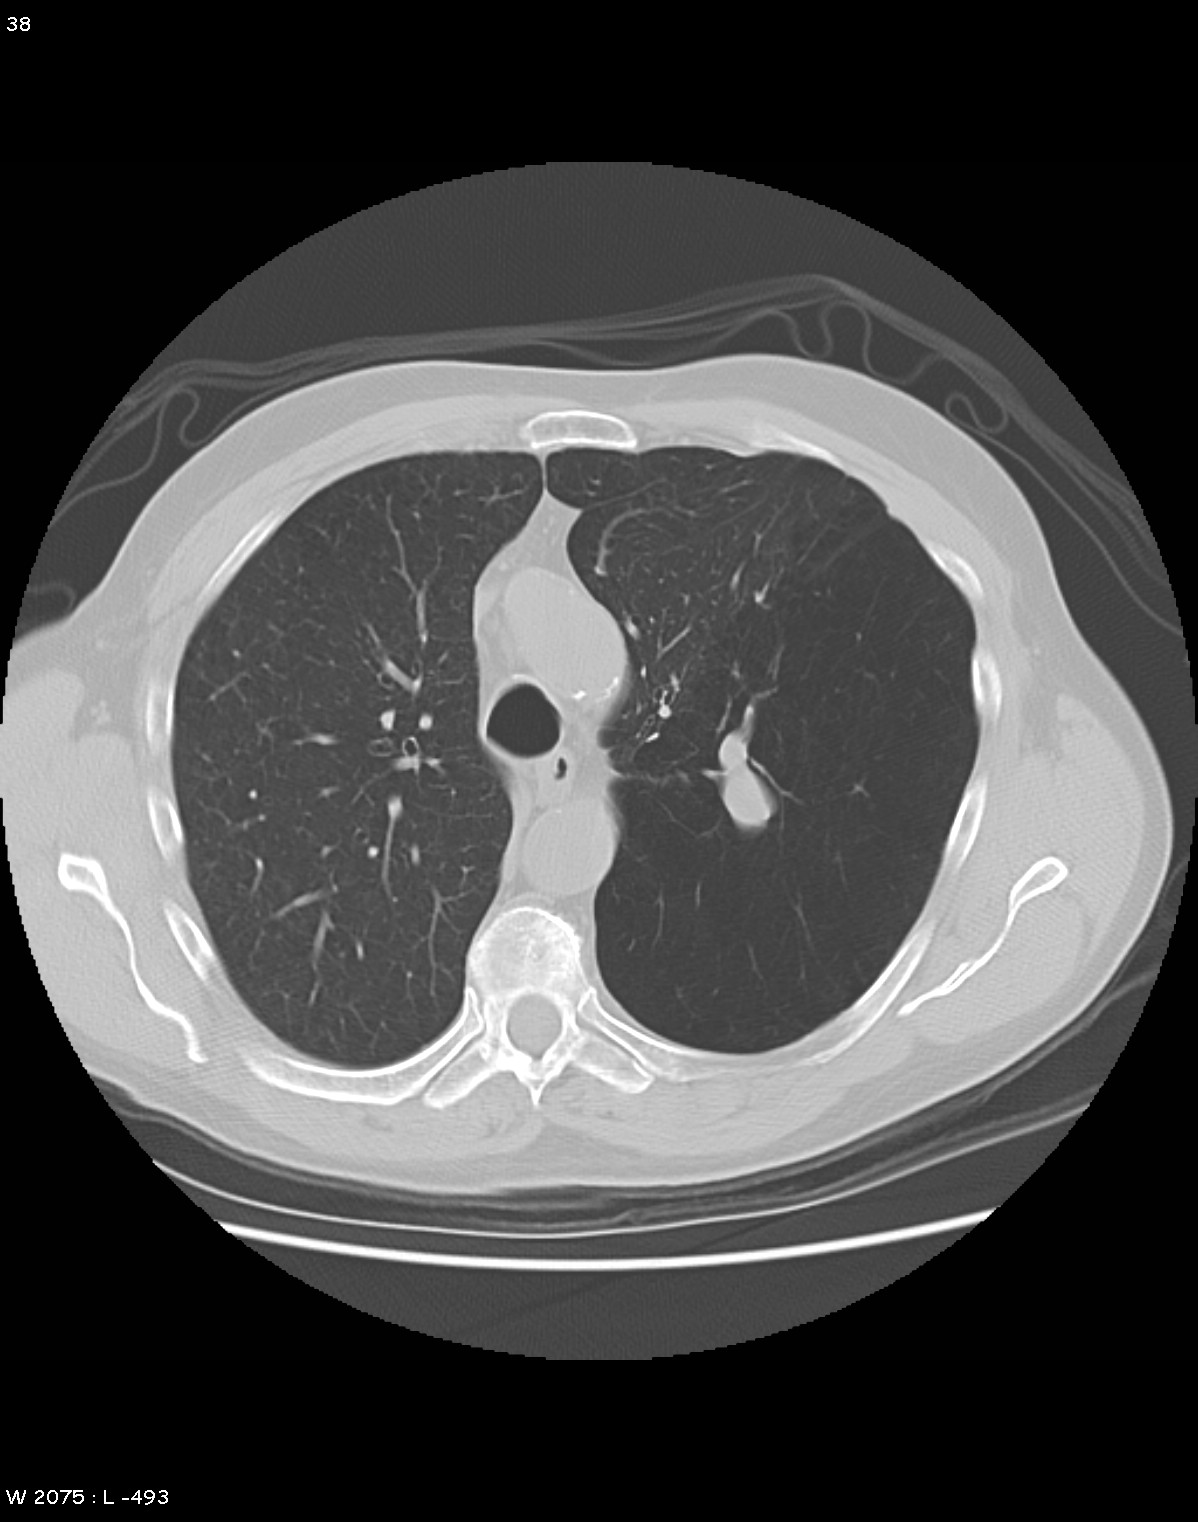

Bronchial atresia CT